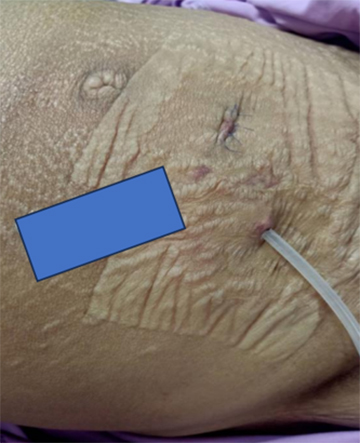

ผู้ป่วยหญิงอายุ 41 ปีรายนี้ ได้รับการวินิจฉัยเป็น lupus nephritis class IV ร่วมกับภาวะน้ำในช่องท้องจากความดันในหลอดเลือดพอร์ทัลสูง ผู้ป่วยมีอาการท้องตึงรุนแรง ต้องเข้ารับการเจาะระบายน้ำในช่องท้องซ้ำหลายครั้ง ส่งผลกระทบต่อการดำเนินชีวิตประจำวันอย่างมาก ไม่สามารถนอนราบ รับประทานอาหาร หรือเคลื่อนไหวได้ตามปกติ (รูปที่ 1) ภายหลังการใส่สาย Tenckhoff เพื่อระบายน้ำในช่องท้อง พบว่าอาการแน่นท้องและหายใจลำบากดีขึ้นอย่างชัดเจน (รูปที่ 2) ต่อมาผู้ป่วยเข้าสู่ ESKD และได้รับการทำ PD แบบเพิ่มระดับ (incremental PD) โดยสามารถควบคุมภาวะน้ำเกินได้ดี มีการนอนโรงพยาบาลเพียงครั้งเดียวจากภาวะน้ำเกิน (รูปที่ 3) และไม่พบภาวะเยื่อบุช่องท้องอักเสบในช่วงติดตามผล 14 เดือน แสดงให้เห็นถึงการปรับตัวต่อการรักษาและคุณภาพชีวิตที่ดีขึ้นอย่างมีนัยสำคัญ ผู้ป่วยสามารถกลับไปใช้ชีวิตประจำวันได้ใกล้เคียงปกติ

รูปที่ 2 หลังใส่สาย Tenckhoff

รูปที่ 3 อาการผู้ป่วยหลังจากใส่สาย Tenckhoff